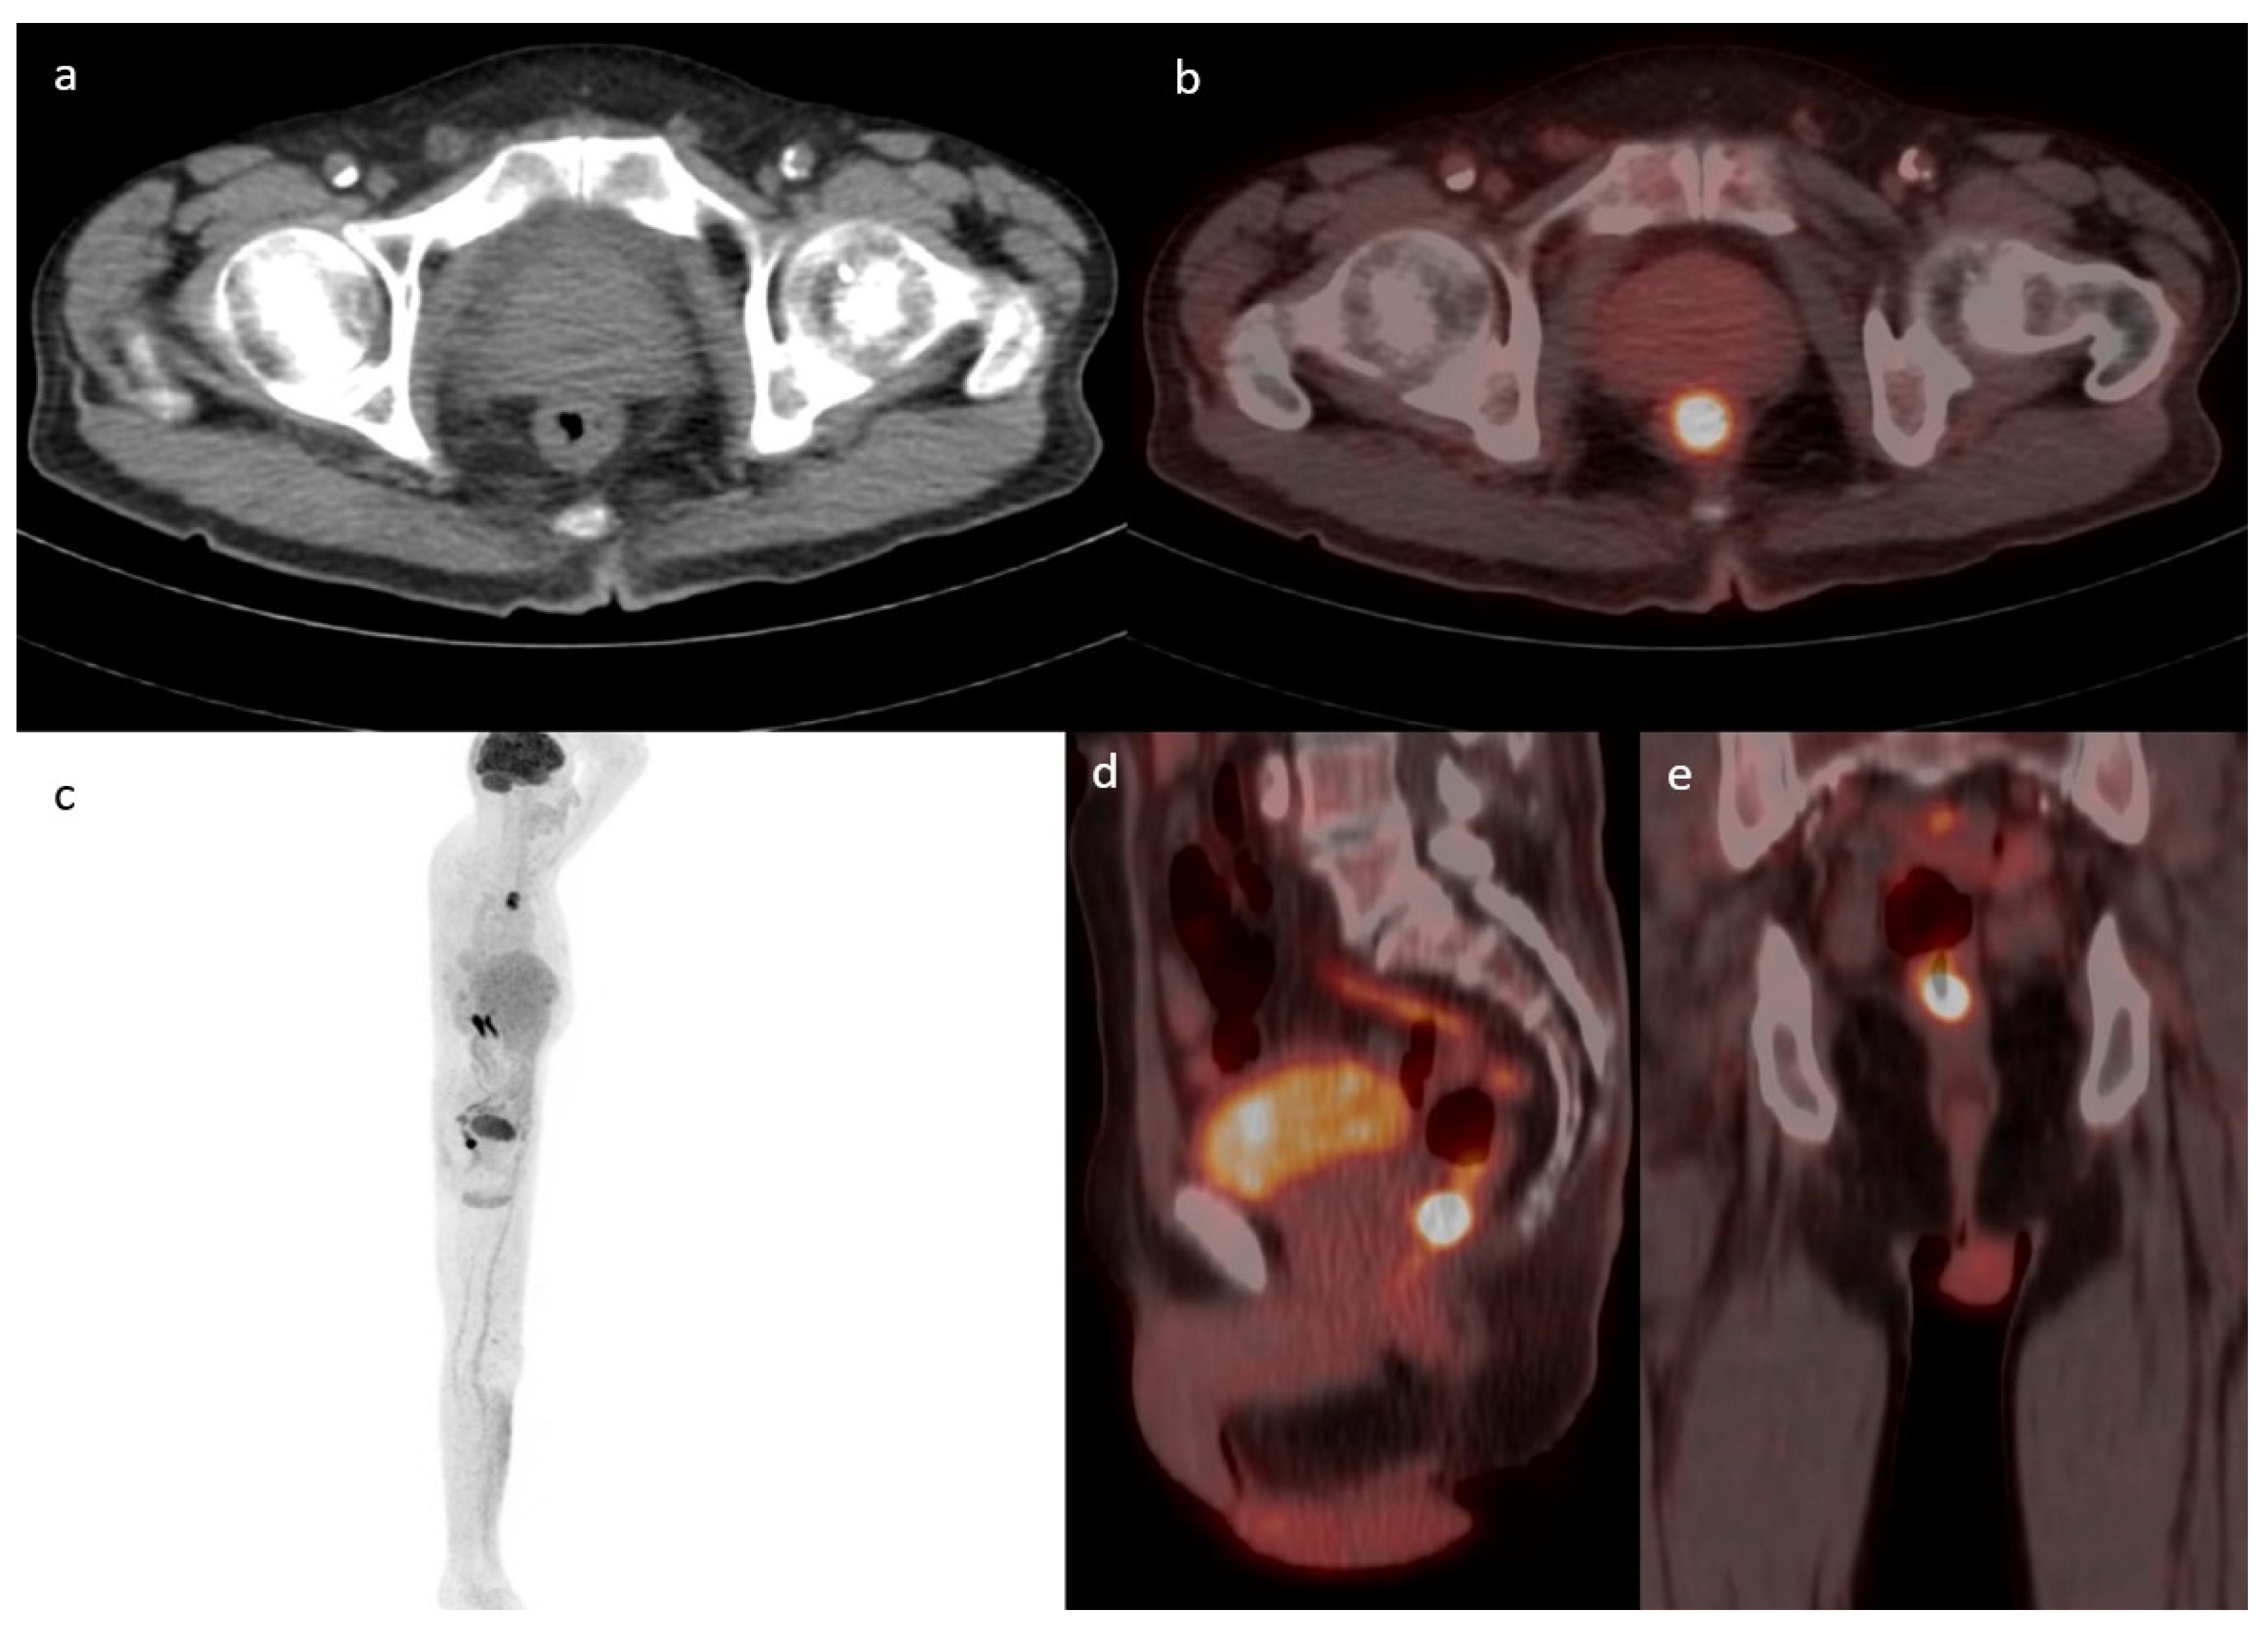

The most common location for incidental GIT uptake was in the upper GIT (n = 212; 48%) followed by the lower GIT (n = 147; 33%), with the rest showing an intestinal or mixed pattern of uptake. One example of lower GIT uptake is presented in Figure 2. The location of upper GIT uptake was in the following order: stomach (174/340; 51%), esophagus (97/340; 29%), and small intestine (69/340; 20%), with 38% (128/340) of the uptake showing multiple localizations in the upper GIT. The location of lower GIT uptake was in the following frequencies: sigmoid colon (77/194; 40%), ascending colon (49/194; 25%), transverse colon (36/194; 18%), descending colon (33/194; 17%), and rectum (1/194), with 25% (47/194) of the uptake showing multiple localizations in the lower GIT.

Figure 2. Case of a 43-year-old female with a history of follicular lymphoma. Axial CT (a) fused with PET (b) showing a focus of increased uptake at the level of the ileocecal valve with an SUVmax of 7.1 corresponding to a 1.7 cm soft tissue density. MIP (c) showing multiple active supra and infra diaphragmatic lymph nodes. The infra diaphragmatic lymph nodes are seen again in the fused sagittal (d) and coronal (e)-fused PET/CT images. The patient underwent a colonoscopy where ileal biopsy showed non-necrotizing granulomas, with no evidence of lymphoma or microorganisms.